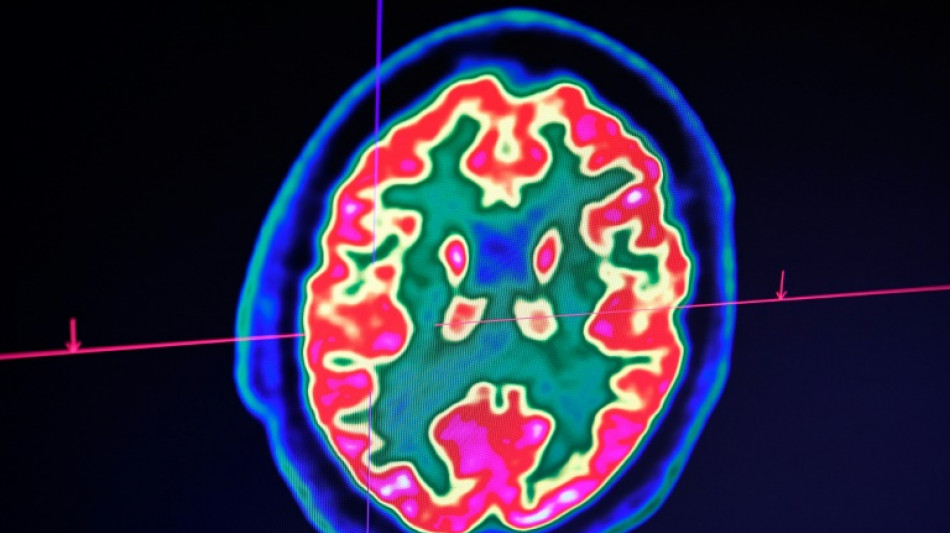

Celle-ci est une maladie auto-immune du système nerveux central (cerveau et moelle épinière). Elle provoque un dérèglement du système immunitaire, qui s'attaque à la myéline, la gaine protectrice des fibres nerveuses.